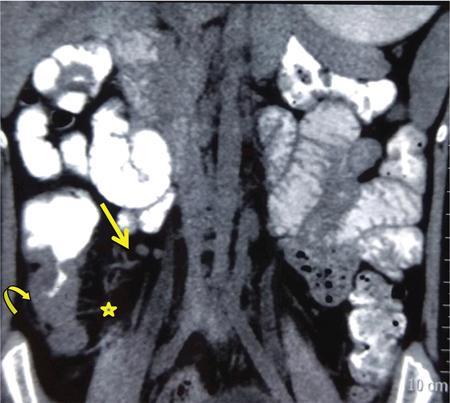

Neera Kohli, Anit Parihar Objectives: To provide the readers with a comprehensive, simplified, lucid, well-illustrated and well-presented latest account of the anatomy, functions, and childhood diseases of the mesentery. Key terms: Mesentery, anatomy, functions, infections, inflammation, neoplasia, cysts, malrotation, vasculitis, textiloma, hernias. Learning objectives: To approach a clinical condition of the mesentery in a logical and comprehensive manner so as to help the patient maximally. Increasing number of researchers, anatomists, radiologists, treating physicians and surgeons are now considering the mesentery as a separate organ. Serious attempt has been made by the authors to stick to the new theory while choosing and describing the various paediatric diseases to be included in this chapter. Likewise, each condition has been described as inclusively as possible. Mesentery develops from the splanchnic mesoderm. It has two parts: a ventral part that forms the mesentery of the abdominal part of oesophagus, the lesser omentum and mesentery of the first part and proximal half of the second part of the duodenum. The other is the dorsal part that runs below the diaphragm, from the oesophagogastric junction to the anorectal junction forming the mesentery of rest of the gastrointestinal tract (GI) including the greater omentum. It consists of fat, and has blood vessels, nerves and lymphatics running that supply the GI. Interest in the mesentery was reactivated when Heald in 1988 demonstrated that tumour recurrence following rectal cancer surgery was dramatically decreased if the mesorectum was removed. Heald’s work was the true start of mesenteric-based surgery. Hohenberger in 2009, focused on the mesocolic region, and showed that intestinal tumour recurrence was minimized, if the mesocolon was surgically excised intact. Heald and Hohenberger thus prompted a renaissance in the study of the mesentery and abdominal anatomy. Following their findings, research was done which demonstrated that the mesentery below the duodenum is continuous, and that the large and small intestine is centrally connected to the rest of the body, by the mesentery. Mesentery originates or has root posteriorly, at the level of origin of the superior mesenteric artery (SMA), as these findings clarified its shape, they marked the start of the scientific study of the mesentery and led to the proposal that it be reclassified an organ. Subsequent research showed that abdominal digestive organs, that is, liver, spleen, intestine and pancreas develop either on or in it. This relationship is retained into adulthood, so abdominal digestive organs are directly connected to the mesentery or we can say that they are ‘mesenteric’ in embryological origin and anatomical position (Fig. 7.10.1). Accordingly, all abdominal and pelvic organs belong either to a mesenteric or a non-mesenteric domain. This model explains the positional anatomy of all abdominal digestive organs and associated vasculature. Moreover, it explains the peritoneal landscape and enables differentiation of peritoneum from the mesentery. Hence, the mesentery should be subjected to the same investigatory focus that is applied to other organs and systems. One should be well versed with the normal appearances of mesentery on USG, CT and MRI (Fig. 7.10.2 A–C). Wherever mesentery is attached, a fascia (Toldt’s fascia) runs between the mesentery and the abdominal wall. This mechanism of anchorage is important. Second mechanism of anchorage involves the peritoneum which lines the abdominal wall and is reflected onto viscera as the ‘peritoneal reflection’. The mesentery, Toldt’s fascia, and peritoneal reflection are continuous. The third mechanism of anchoring is the vascular pedicle. Further mesenteries may be divided into true and specialized mesenteries. True mesenteries connect abdominal organs to the posterior wall of the abdominal cavity. These are the small bowel mesentery, the transverse mesocolon, and the sigmoid mesentery. Rest are specialized mesenteries. They do not attach organs to the posterior wall of the abdomen. The mesenteric organ is responsible for the development of systemic inflammation, such as the systemic inflammatory response syndrome (SIRS) and multiple organ dysfunction syndromes (MODS). Proinflammatory cytokines are produced in the intestine and mesentery and are then systemically distributed via mesenteric lymph. These contribute to a systemic inflammatory response, for example, post injury. The mesentery comprises a connective tissue lattice within which adipocytes are present in large numbers. Due to production of cytokines like C-reactive proteins (CRP), resistin, leptin and adiponectin by the mesentery it is considered responsible for glycemic/lipidemic disorders. Mesentery is a big source of secretion of CRP as it contains the largest part of visceral fat hence it is being implicated in diabetes and metabolic syndrome, suggesting that mesenteric adipocytes play a role in the pathobiology of these disorders. Further, visceral tissue plays an important role in immune regulation and may function as a proinflammatory agent. In mesenteric inflammation, both tissue and circulating fibrocyte levels are elevated and are associated with autoimmunity (e.g. systemic scleroderma, rheumatoid arthritis, Grave’s disease), inflammation, and fibrosis (idiopathic pulmonary fibrosis). These can differentiate into adipocytes or fibroblasts and are associated with autoimmunity in conditions such as: systemic scleroderma, rheumatoid arthritis, Grave’s disease and idiopathic pulmonary fibrosis. Fibrocytes also have the ability to act as proinflammatory cells by secreting cytokines. Although currently neutrophils, lymphocytes, adipocytes, and fibrocytes are being studied in details, it is quite possible that there are other varieties of cells involved in mesenteric inflammation. ANML, also known as primary mesenteric lymphadenitis, is a self-limiting inflammatory disease of the mesenteric lymph nodes of right lower quadrant. Clinically it closely resembles acute appendicitis (AA). It occurs in children, adolescents and young adults. CRP and leukocyte count do not help much in differentiating these two conditions. Ultrasonography is the investigation of choice for diagnosing ANML. If three or more mesenteric lymph nodes with a short-axis diameter of 8 mm or more without any associated inflammatory process is identified then ANML is a strong possibility (Fig. 7.10.5A and B). CT if needed, is usually reserved for older patients. Radiologists should try to visualize the appendix as well. If the appendix is normal then it favours diagnosis of ANML. Occasionally, very large mesenteric lymph nodes may result in vascular compromise leading to ischemic colitis. Secondary mesenteric lymphadenitis is associated with some detectable intraabdominal inflammatory process. ANML is more common than AA in the first decade of life. AA becomes more frequent in the second decade and is distinctly uncommon after the age of 20. Boys are more commonly affected. Common symptoms are: fever, vomiting, change in consistency and frequency of stools and mild pain to severe colic. The pain mimics that of AA as it is felt in the right iliac fossa as well as in the periumbilical area. Although, this condition is referred to as nonspecific yet causative micro-organisms have been identified. These are: Several viruses, Yersinia enterocolitica, Helicobacter jejuni, Campylobacter jejuni, Salmonella spp., Shigella spp. and Mycobacterium tuberculosis. Yersinia enterocolitica is considered the most common pathogen in temperate regions. It has been observed that, when ANML or appendicitis occurs in childhood or adolescence, there is a significantly reduced risk of ulcerative colitis later in life. CD is a chronic inflammatory disease that affects the GI and adjacent mesentery in the paediatric and adult populations. Its prevalence is increasing worldwide. Mesentery of patients with CD has more fat tissue. These fat cells can produce proteins such as CRP which is associated with inflammation. This may be the cause of increased inflammation and bacterial invasion. Imaging studies have very vividly shown mesenteric and intestinal involvement in CD. Following are the findings noted in CD of the mesentery: Increased vascularity, oedema, lymphadenopathy, proliferation of the fibrous and fatty tissue, and increased density of fat. Besides these, stenosis and sacculations in the mesentery are also seen. Computed tomography (CT), magnetic resonance (MR) enterography, and strain elastography findings are demonstrated equally well in the mesentery and contiguous intestine. CT enterography is a better modality for assessing mesenteric abnormalities. Sakurai et al. have demonstrated radiological evidence of mesenteric hypervascularity (‘comb sign’) and nodal enlargement correlated with endoscopic evidence of mucosal ulceration. Gale et al. compared MR and CT enterography findings in 84 children and adolescents having active CD with radiological findings in their mesentery. They concluded that mesenteric hypervascularity, oedema, fibrofatty proliferation and lymphadenopathy correlated well with active mucosal disease. Mesenteric vascular diseases like arterial emboli, venous thrombi, and venous congestion have been reported in CD. These may be complicated by bowel ischemia and perforation. Lymphoma may arise in the mesentery in CD, without involvement of other organs, so neoplasia must be considered as a differential of a mesenteric mass arising in CD. It was first reported as retractile SM in 1924. SM is a rare, benign idiopathic, chronic, fibroinflammatory disease of the small bowel mesentery. It is of three types: mesenteric lipodystrophy, mesenteric panniculitis and retractile mesenteritis. Prevalence of mesenteric panniculitis is 0.6%. All three have distinct radiographic features, however, there is considerable overlap. Mesenteric panniculitis (MP) is a localized, chronic inflammatory process, seldom advancing to become fibrosis which may be florid. SM on sonography is seen as a hyperechoic, vessel encasing mass. This mass can also cause adjacent bowel displacement. This same feature is seen as halo sign on CT but without occlusion. CT can also show significant lymphadenopathy, bowel displacement and increase in the enhancement of surrounding fat labelled as ‘misty mesentery’, which is characteristic of MP. These findings are useful in differentiating SM from lymphomas and desmoids. The soft tissue nodules and calcifications in the vicinity are encased by dense tissue and fat leading to formation of a ‘pseudocapsule’. Though ‘Halo sign’ and ‘pseudocapsule’ are dependable signs yet they do not qualify to be called pathognomonic for SM. On the other hand, MRI has a higher sensitivity than CT for detecting SM. On MRI, mesenteric panniculitis and scattered lymph nodes are hyperintense on T2WI. In contrast, retractile mesenteritis has numerous strands of soft tissue, due to fibrosis with low signal on T1WI and T2WI MRI. Tuberculosis of mesenteric lymph nodes, along with peritoneal tuberculosis is seen in 45%–80% of children with an abdominal disease. Mesenteric lymph nodes involvement is seen frequently. Lymph nodes can get involved through lymphatic drainage of infected organs, retrograde lymphatic spread from intrathoracic disease, or due to hematogenous spread (Fig. 7.10.6). Tuberculosis of intraabdominal lymph nodes may occur without involvement of the intestine and peritoneum (Fig. 7.10.7). In such cases, it is associated with enlarged extra-abdominal superficial lymph nodes. The diseased involved lymph nodes may regress over time with or without calcification, can form inflammatory masses with possibility of abscess formation later on. Fistulae and ascites may also be seen. Ultrasound is the investigation of choice. Generally, lymph nodes show a central hypoechoic area due to central liquefaction; they can form conglomerates and infiltrate the omental fat, forming omental cake. Ultrasound also detects ascites very well. Ascitic fluid may be clear or contain fibrin strands, loculations and debris. The differential diagnosis of ascitic septations includes lymphoma, other carcinomas, and pyogenic peritonitis. Echogenicity of mesentery is increased in mesenteric tuberculosis. CT has a greater sensitivity than ultrasound in detecting mesenteric lymphadenopathy. Presence of lymph nodes with calcifications or with the typical low-density centres due to liquefaction and a peripheral ring enhancement favours tuberculosis. Solid organs like liver and spleen can have calcification. CT can easily detect inflammatory masses consisting of lymph nodes, omentum and bowel (called omental cakes). In children, MRI has the usual advantage of the fact that there is no ionizing radiation. However, sedation may be required due to a long study time. MRI findings of TB lymphadenitis display a predominant peripheral rim enhancement with or without a multilocular appearance, with a central non-enhancing lesion corresponding to caseation or liquefactive necrosis. Ascitic fluid is seen very well as a T2WI hyperintensity. Radiograph of the chest is a supportive investigation as 23% patients of proven pulmonary tuberculosis also have abdominal disease.